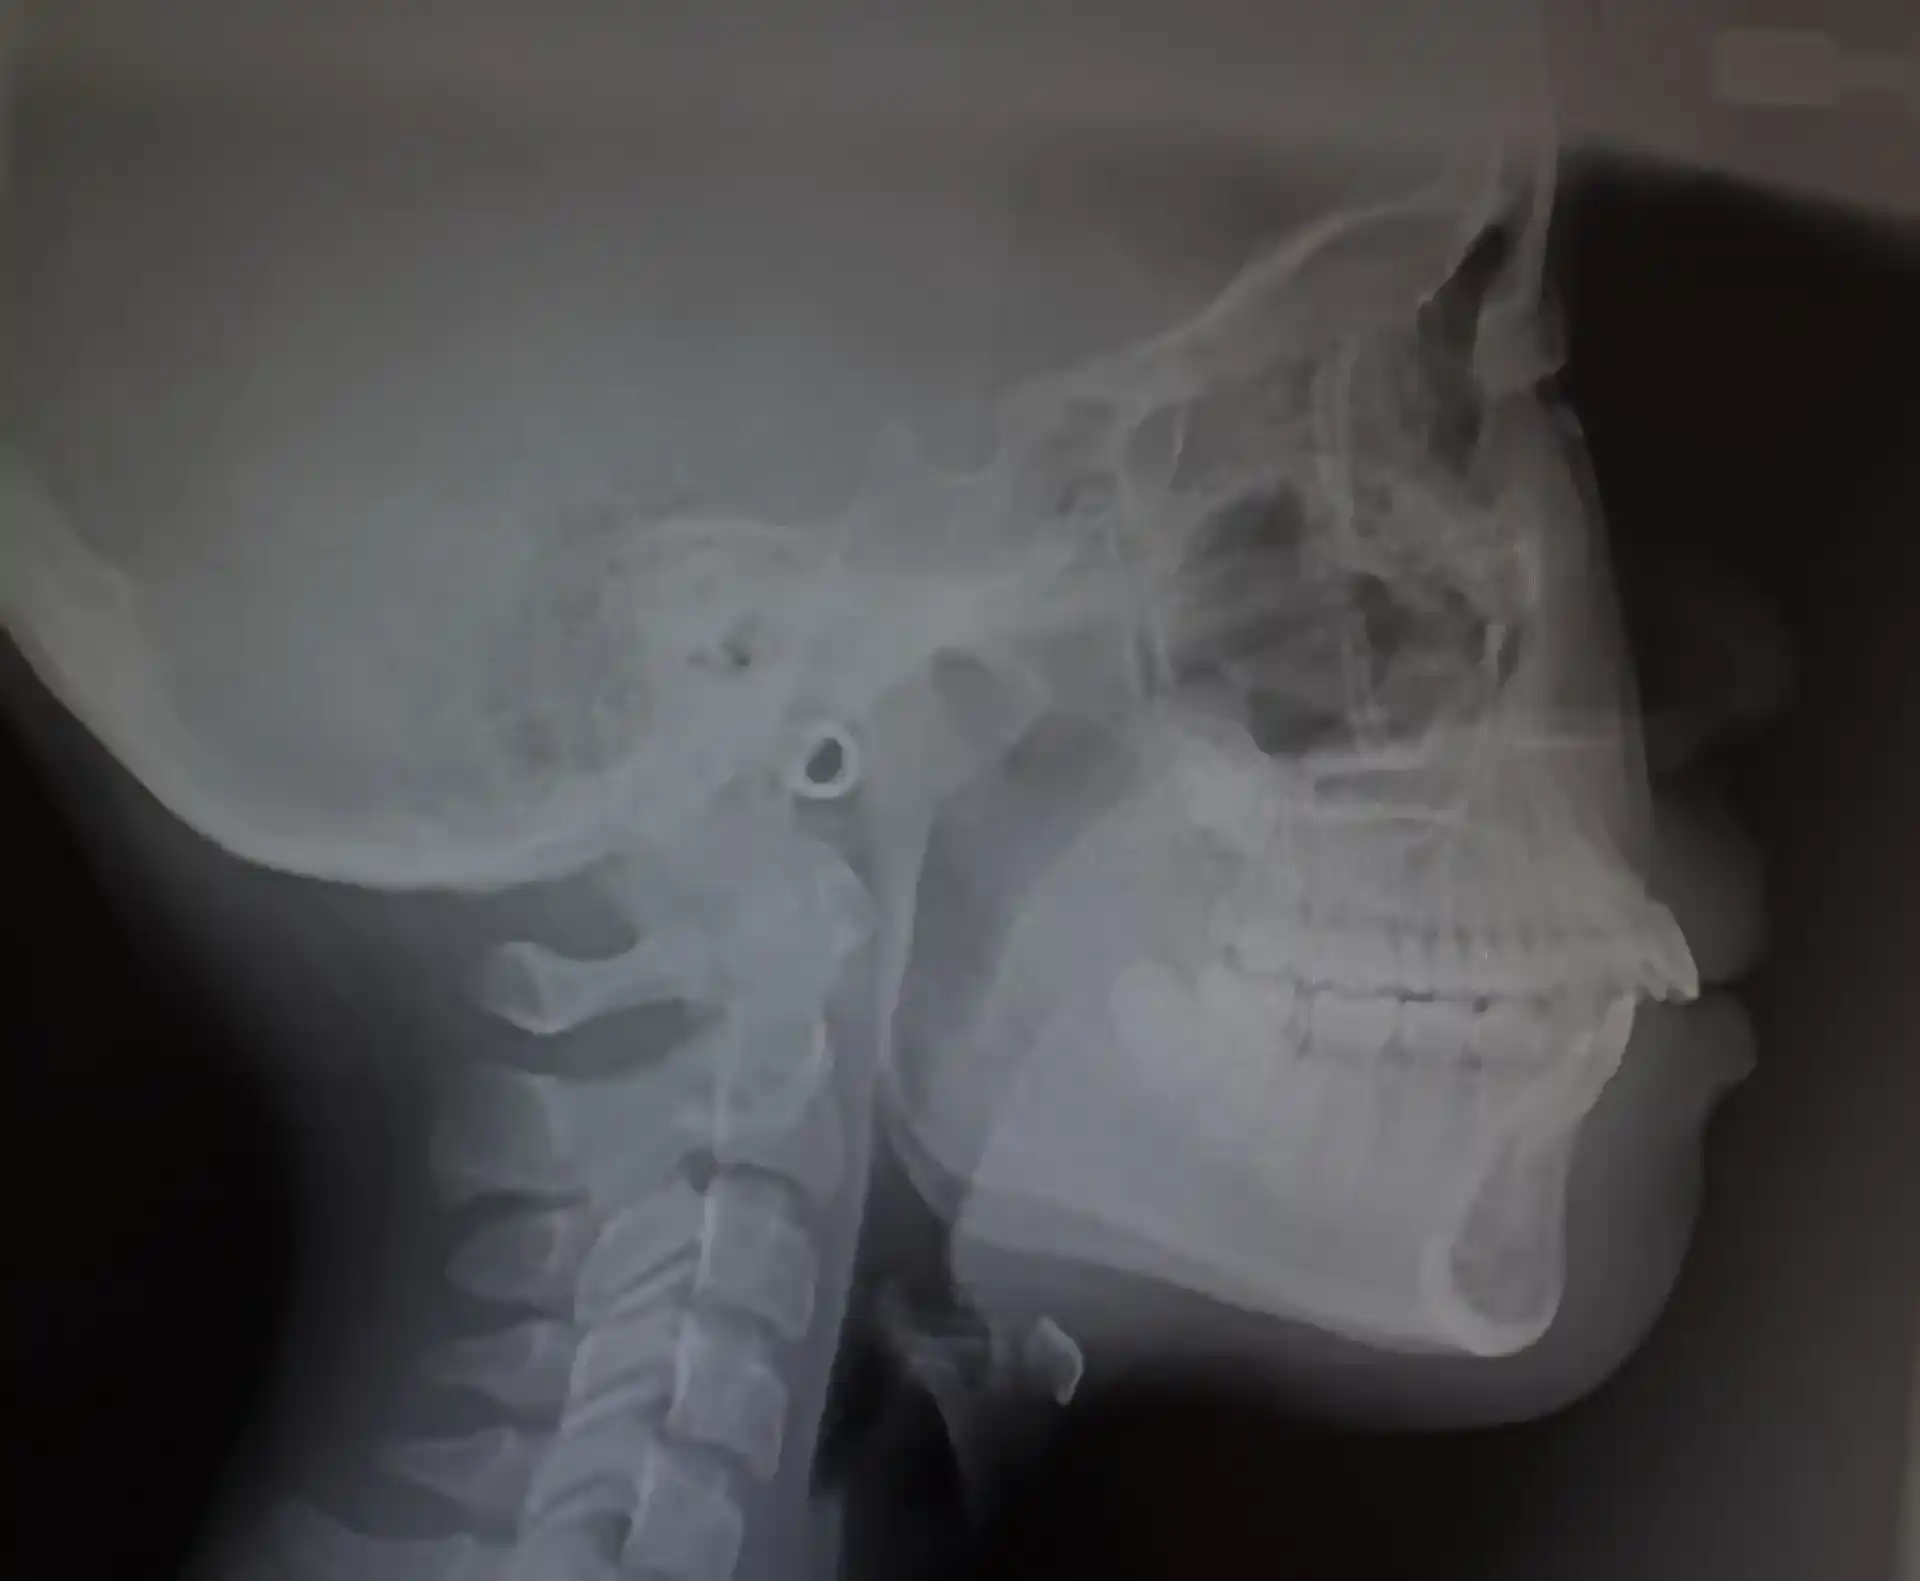

レントゲンの分析でガミースマイルや口元の見え方は骨格と歯の傾きによるものとわかりました。骨格の傾きにより口元の筋肉も影響を受け、その結果笑った時の口元に歪みが生じていました。そのため、ワイヤーによる矯正だけでなく、口元の動かし方も含めてトレーニングを行い理想の笑顔を作れるような治療の目標を立てました。

アンカースクリューにて歯の位置を調整しています

歯の位置をアンカースクリューにて調整しています。